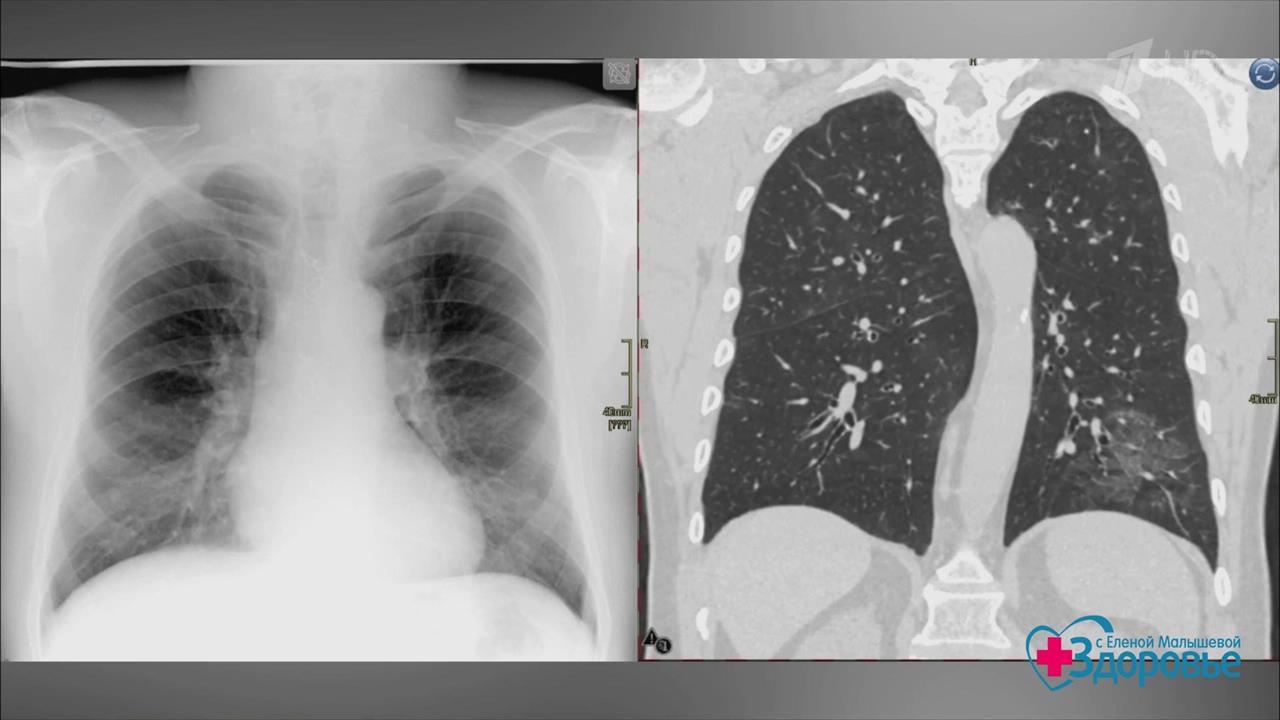

Коронавирусная пневмония. Как лечить? Здоровье. Фрагмент выпуска от 10.05.2020

Вирусная пневмония – грозное осложнение коронавируса COVID-19. Как ее лечить? Говорим о самых новых разработках с экспертом программы. В студии – главный рентгенолог Москвы Сергей Морозов.